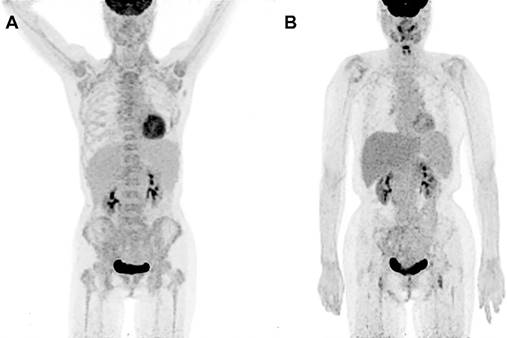

PET/CT metabolic parameters including SUVmaxBM and SUVmaxBM/Liver were summarized in TABLE 3. The receiver operating characteristic (ROC) curve showed that SUVmaxBM had higher area under curve (AUC) for diagnosing bone marrow MI (AUC=0.772, 95%CI: 0.645-0.899) with the best cutoff value of 6.15. Using SUVmaxBM of 6.15, the sensitivity and specificity for diagnosing MI were 47.6% (10/21) and 100% (63/63). Figure 1 shows two patients diagnosed with acute lymphoblastic leukemia and bone marrow hyperplasia, in which the SUVmaxBM were 9.1 and 4.5, respectively.

Increased diffuse BM uptake on PET images. (A) A 49-year-old woman was diagnosed with lymphoblastic leukemia from bone marrow biopsy. Both axial and appendicular skeleton had diffuse FDG accumulation. The SUVmax of bone marrow was 9.1, which was higher than the cutoff value (6.15). (B) A 41-year-old woman was diagnosed with bone marrow hyperplasia by bone marrow biopsy. Diffuse FDG accumulation was distributed mainly in axial skeleton. The SUVmax of bone marrow was 4.5, which was lower than the cutoff value (6.15).